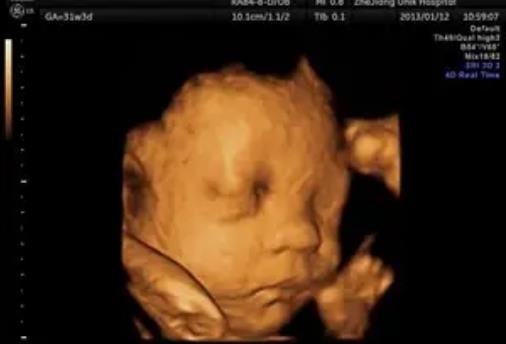

雖然懷孕的時候醫(yī)生是絕對不會告訴家長胎兒性別的,但大多數(shù)家長還是按捺不住好奇心,總想自己從各種檢查單子上看出男女差異。網(wǎng)上一直流傳懷女孩的標(biāo)志是圓形的孕囊,要是B超單有這個一般是女孩,那么現(xiàn)實真是這樣嗎?除了孕囊還有別的懷女孩標(biāo)志嗎?下面小編就帶大家來了解一下。

1、圓形的孕囊:B超單上可以看到孕囊,要是孕囊是長形的,那么就是男孩,要是孕囊呈圓形或橢圓,那可能就是女孩。

2、較高的胎心率:女寶寶的胎心率一般在150以上,而男寶寶的胎心率一般在140左右。

3、背朝外的胎位:這是由很多孕媽發(fā)現(xiàn)的規(guī)律,女孩子喜歡背朝外,面朝里,姿勢很像在和媽媽擁抱一樣。

4、雙頂徑和股骨的差小于2:雙頂徑是胎兒頭部的橫向長,而股骨則是胎兒大腿骨的長度,由于男女體型差異,女孩子的頭和腿的差異很小,一般都會小于2。

以上就是網(wǎng)上流傳的生女孩的標(biāo)志,但只要生過孩子的人都知道,這其實一點科學(xué)依據(jù)都沒有,只是為了滿足寶爸寶媽的好奇心而已,大家看看就行,不要當(dāng)真,最重要的還是胎兒的健康發(fā)育。